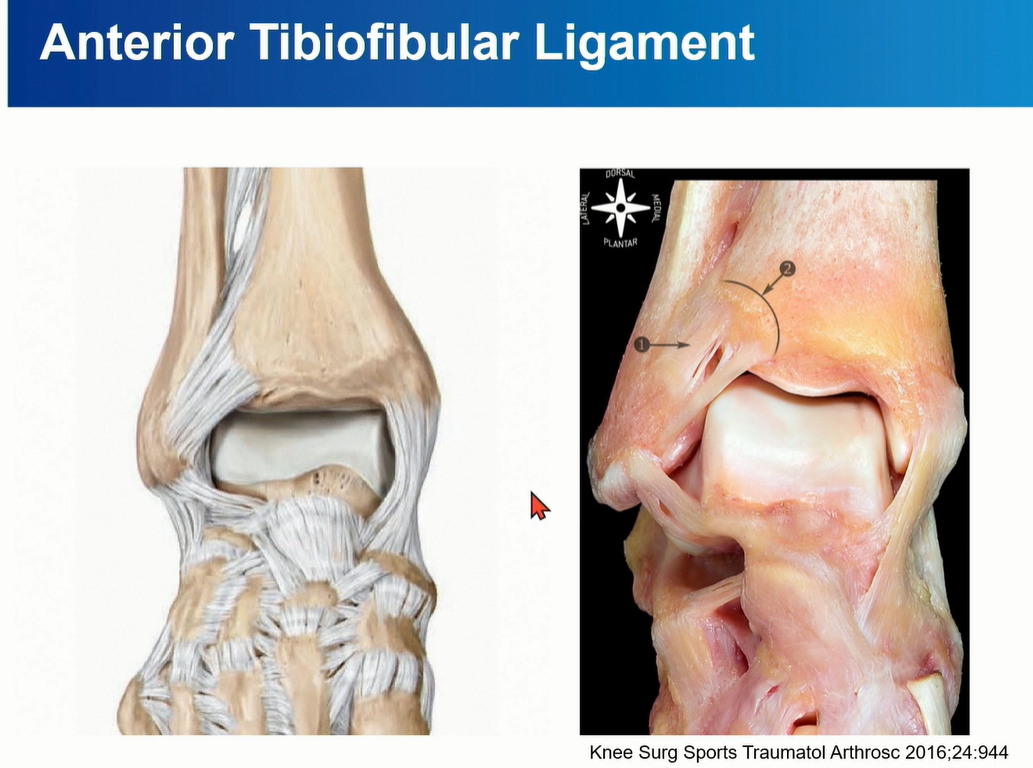

4-2. ATTFL

Tibia plafond의 anterolateral tubercle에서 시작해서 distal fibula에 붙고, 비스듬하게 여러 가닥으로 구성되어 있다.

AITFL의 가장 inferior bundle은 main bundle에서 떨어져 있는데, 이 fiber를 Bassett's ligament 라고 부른다. Talus와 impinge를 일으키기도 하는데, anterolateral ankle impingement를 뜻함.

MRI에서는 coronal cut에서 AITFL 를 관찰하기 용이하다. Multi-fascicular 구조이기 떄문에, Tear로 오인하면 안됨.

특히 Axial cut에서는 일부 cut에서 discontinuity 가 관찰될 수 있는데, oblique한 주행 방향으로 인한 정상 소견일 수 있다는 것을 염두해야 한다.